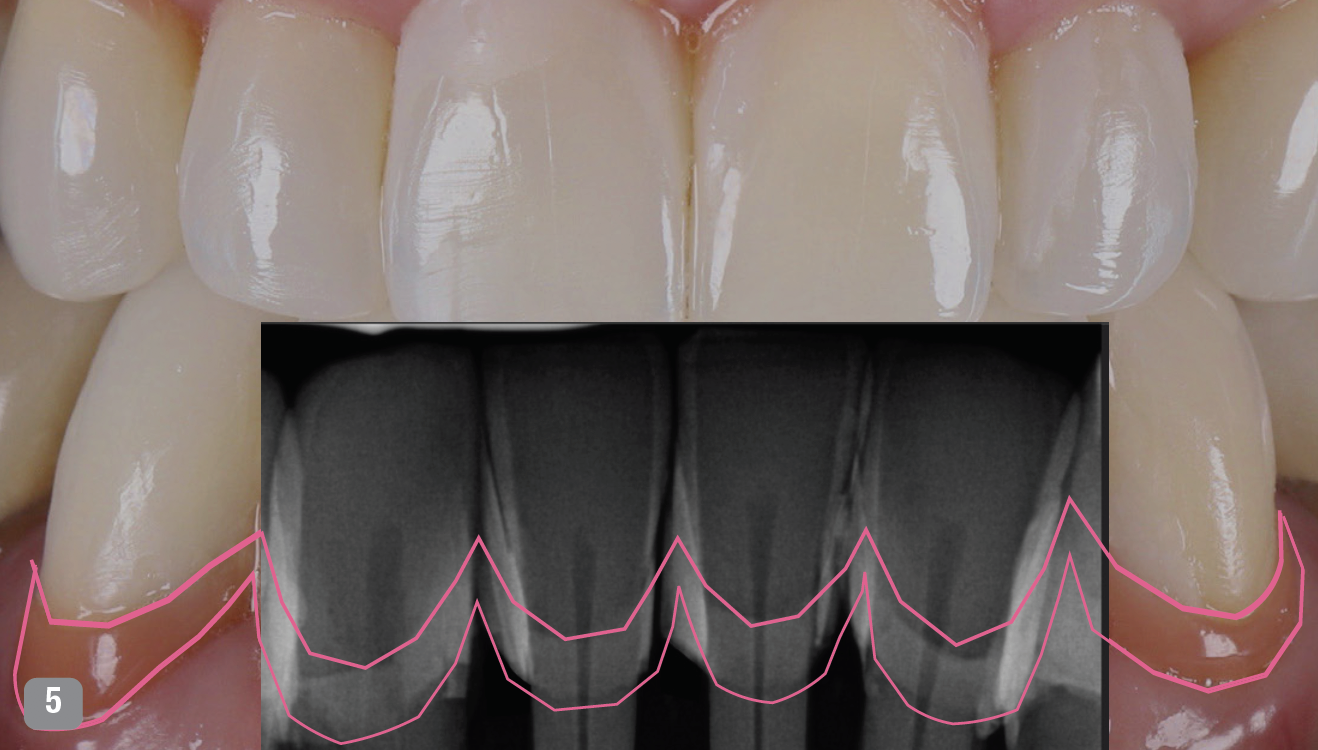

Figure 5 shows radiographs on Cody's anterior teeth that were indicated for treatment. His gingival recession and bone loss already had been classified, and he had already had orthodontics; Cody did not need orthodontics again, but it is an option in many such cases. Possible options were porcelain veneers on both the mandibular and maxillary teeth, porcelain crowns, and splinted bridges on the mandibular anterior-requiring compromising and removing a lot of tooth structure. Removal of mandibular incisors with implant placements was another option, as was a four unit bridge with or without orthodontic extrusion-knowing that as teeth are extruded, tissue and bone will be pulled with them as well.3

In the case of Cody, after doing the digital smile design, whitening was called for, and afterwards the patient was diligent with his hygiene. Before treatment, the patient presented with calculus, and so hygienist removed it before any other procedures, as teeth have to be clean at the beginning. Patient was augmented with white and pink. Figures 5 and 6, with Figure 5 showing the radiograph superimposed, show the progression. Procedures took only a few hours, and patient was so pleased he asked for additional improvements, which have included grafting and replacement of posterior crowns. Figure 6 was taken one-year post-treatment. Patient and his wife actually wrote a letter offering thanks for allowing Cody to feel proud of his smile for the first time in his life.

Fig 5. Superimposed over the photograph, a radiograph of the patient's anterior teeth show existing bone loss.

Figure 5